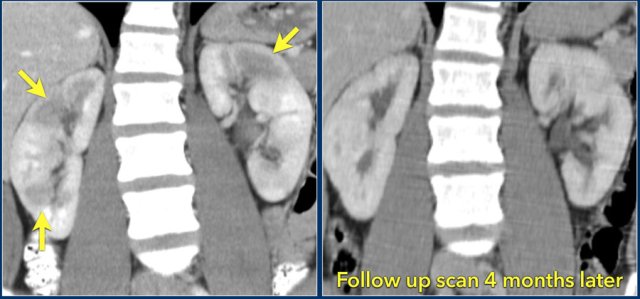

In this case there are hypodense areas in both kidneys.

Based on the imaging alone the main differential is multifocal pyelonephritis, lymphoma and metastases.

This patient had a urinary tract infection and episodes of flank pain and there was no history of a primary tumor or lymphoma.

So the diagnosis is pyelonephritis.

A CT scan 4 months later shows normal enhancement of both kidneys; the renal abnormalities on the first scan were therefore consistent with an episode of multifocal pyelonephritis.